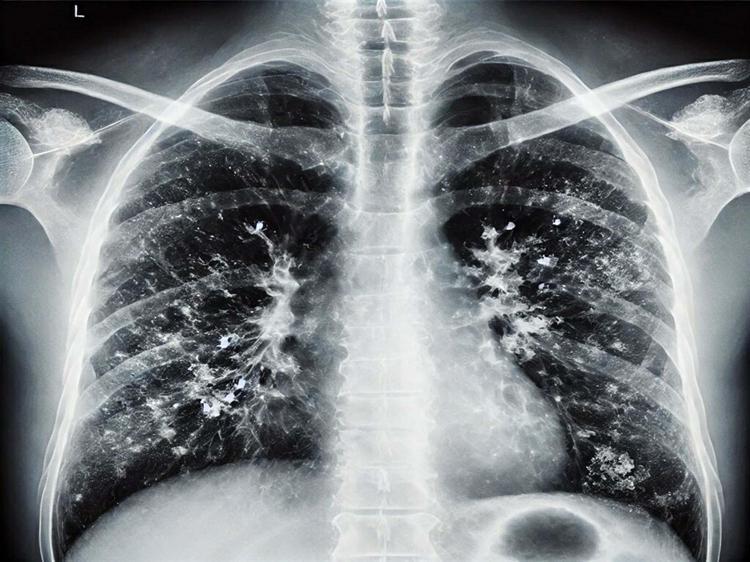

'Kışın solunum yolu enfeksiyonlarında artış doğal, hijyen şart'

İzmir'de İl Sağlık Müdürlüğü Halk Sağlığı Hizmetleri Başkanlığı Başkan Yardımcısı Doktor Metin Kızılelma, kış aylarında solunum yolu enfeksiyonlarında artışın doğal ve bu enfeksiyonlardan korunmanın en önemli etkenin ise 'hijyen' olduğunu söyledi.